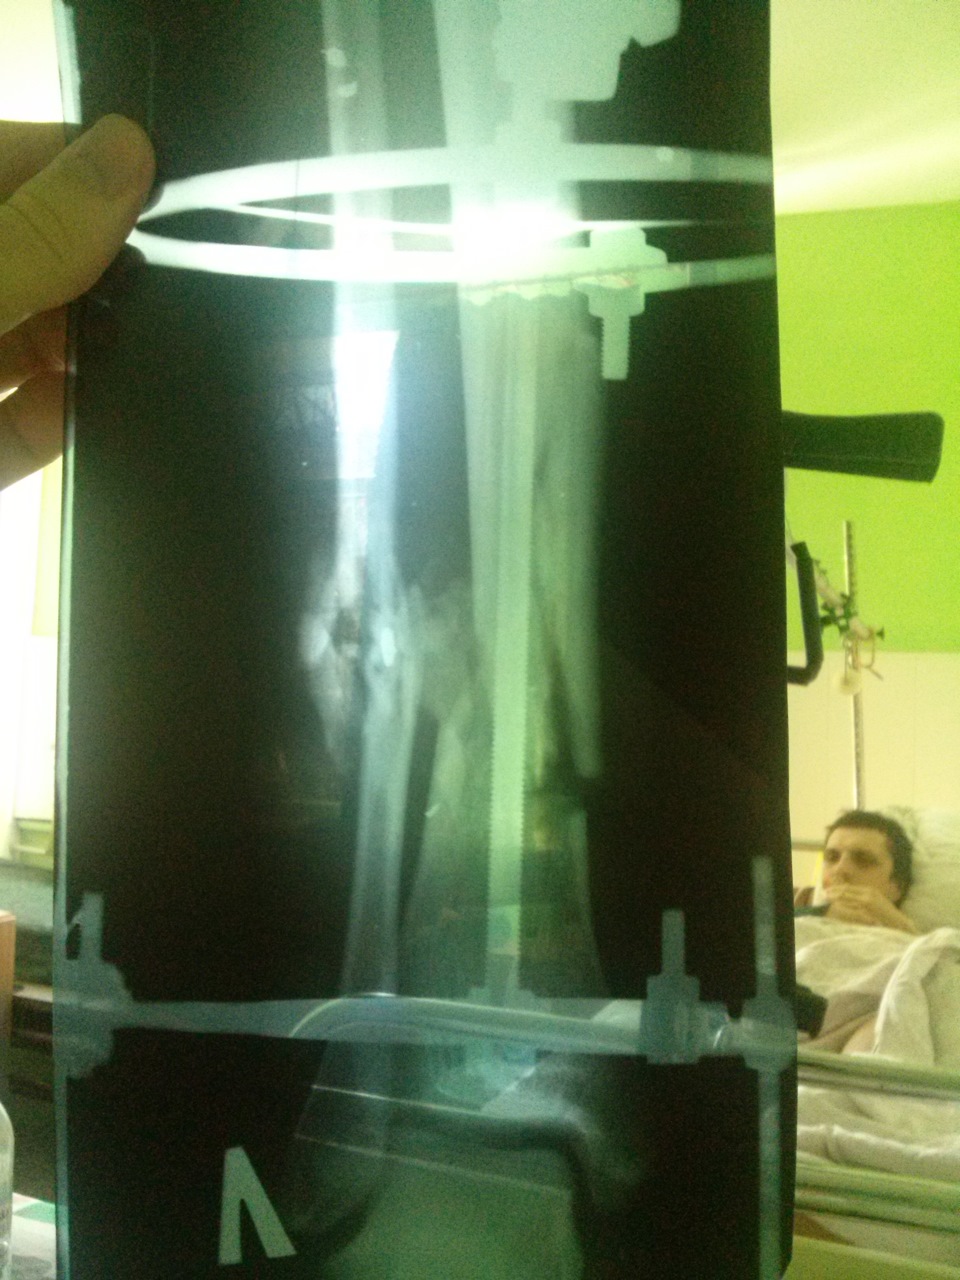

Фиксация костей стержневым аппаратом наружной фиксации

Нога после установки аппарата наружной фиксации

Установка аппарата

После проведённого обследования пациента доставили в экстренную операционную. Там ему хирургически обработали рану и зафиксировали кости левой голени и стопы с помощью стержневого аппарата наружной фиксации. После операции мужчину госпитализировали в отделение реанимации для дальнейшего лечения и динамического наблюдения.